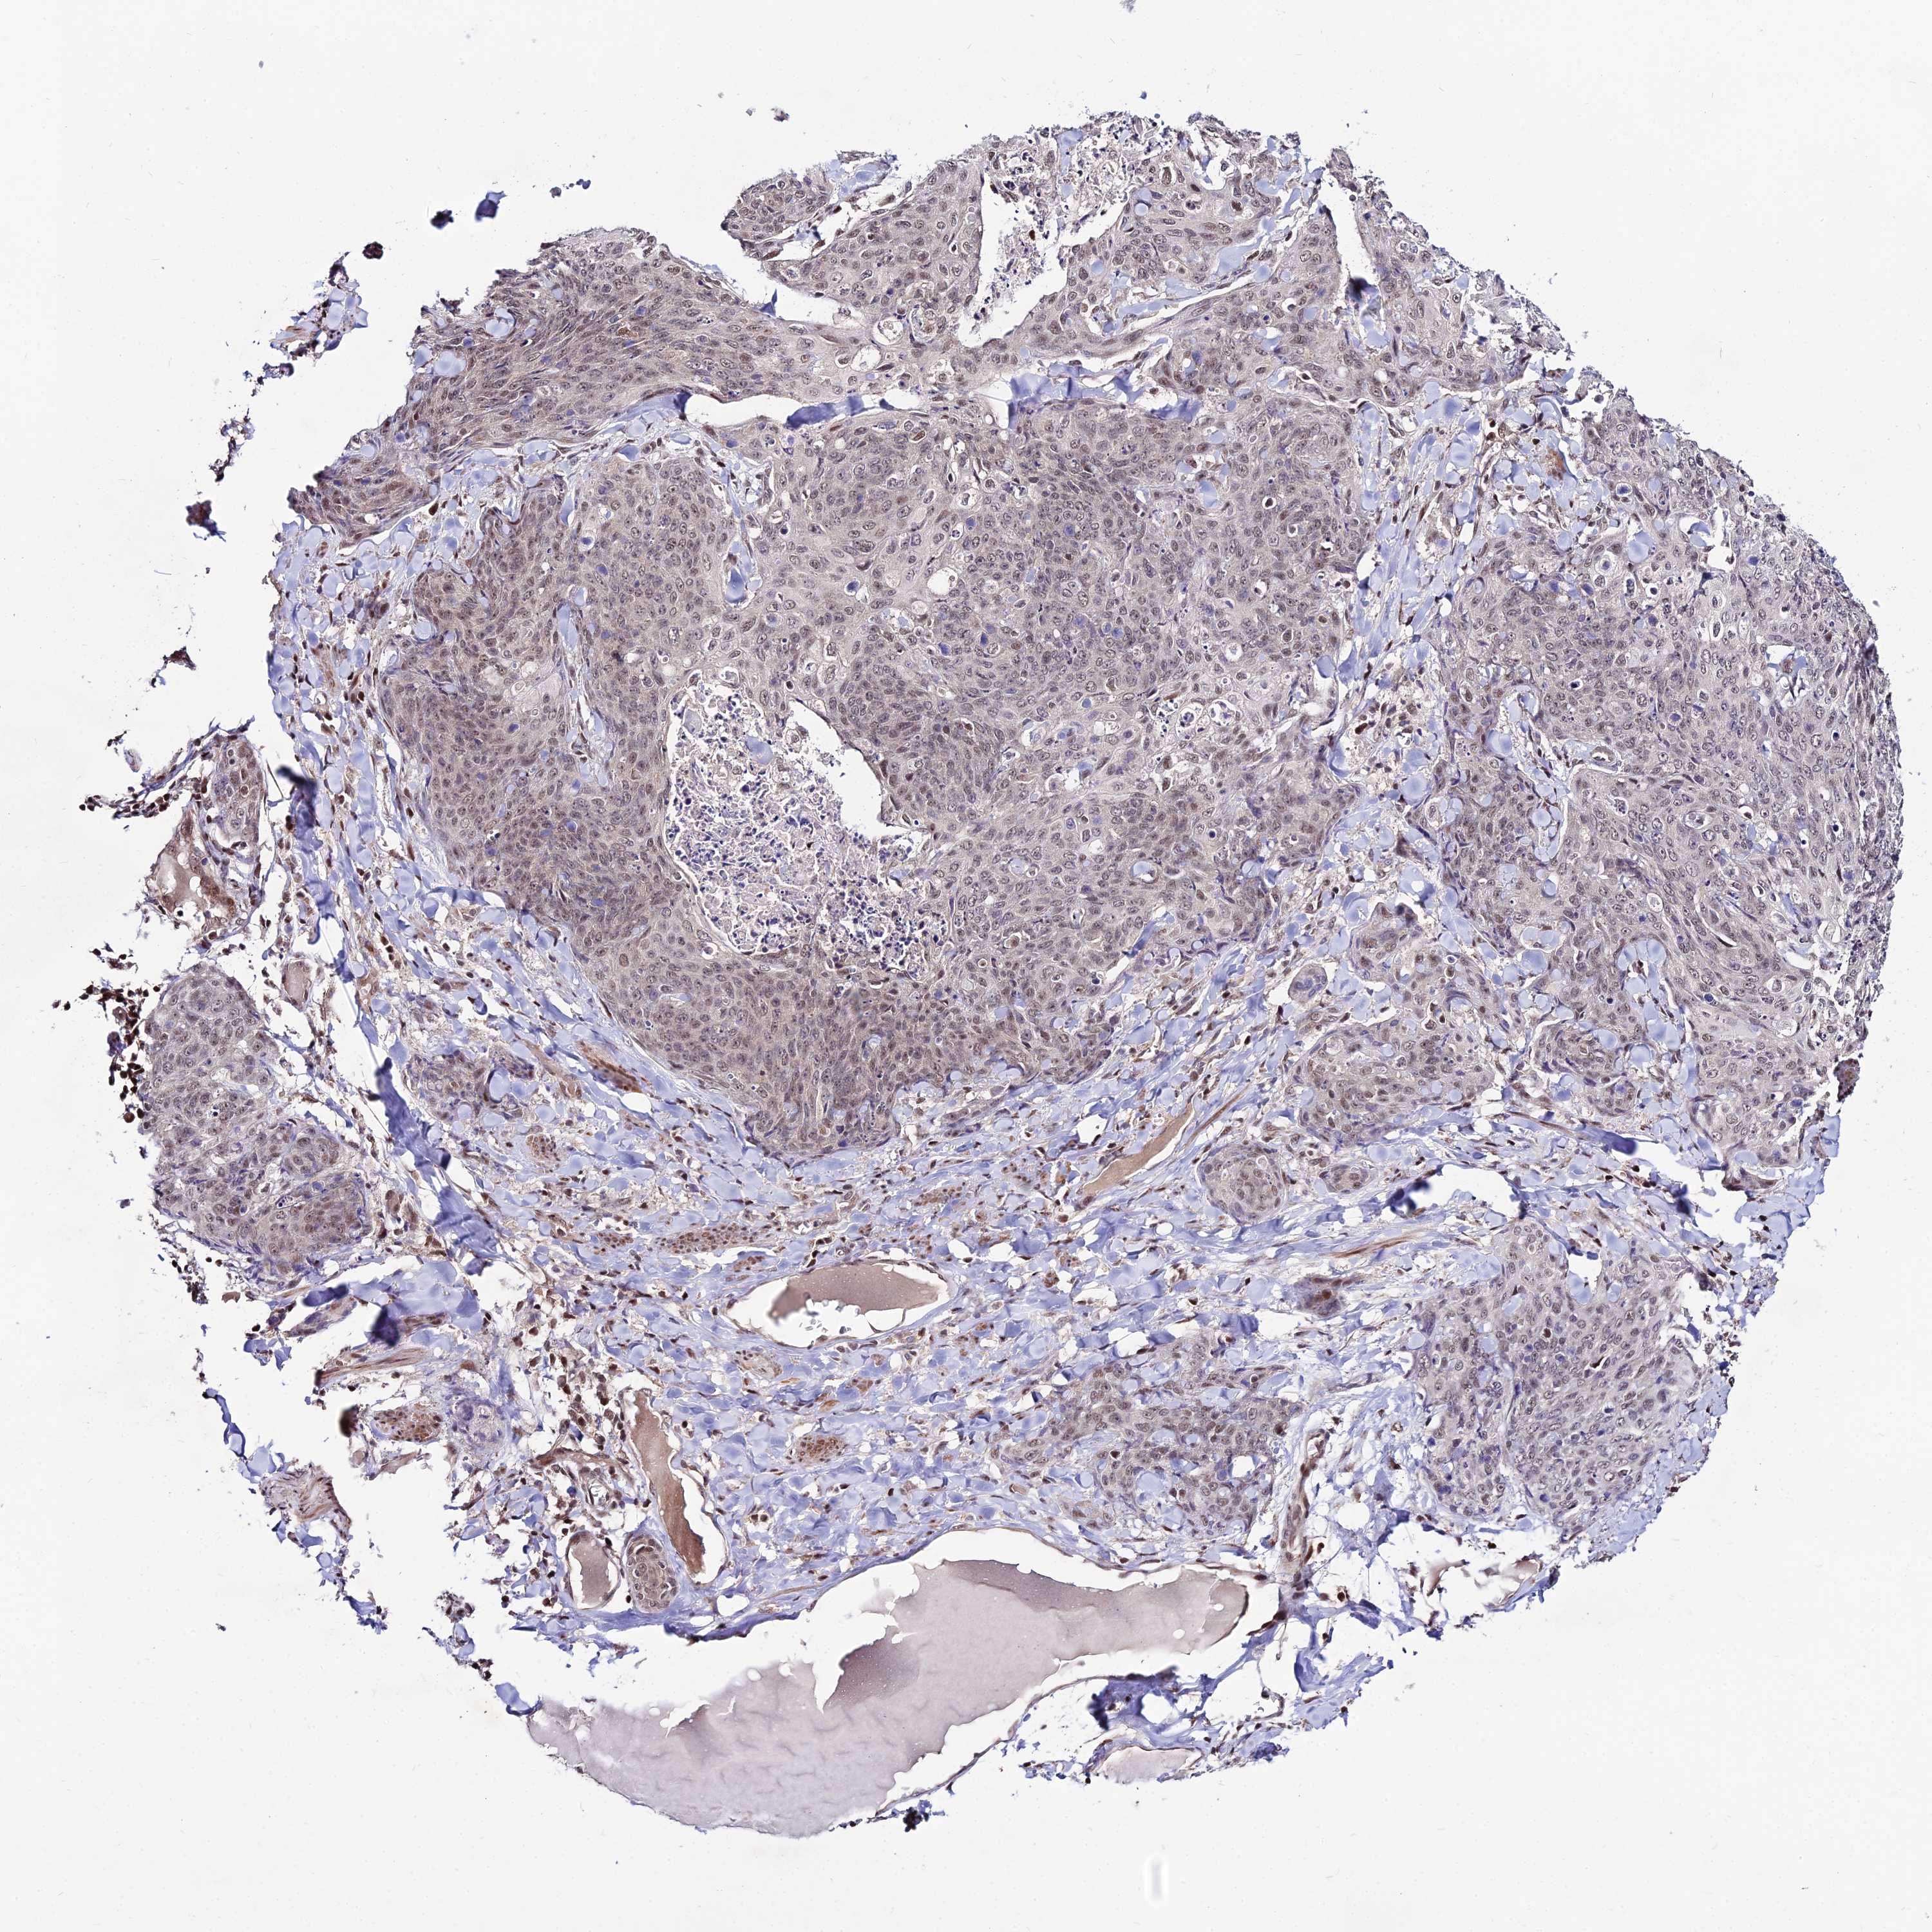

SKIN CANCER - Protein expressioni

A mouse-over function shows sample information and annotation data. Click on an image to view it in a full screen mode. Samples can be filtered based on level of antibody staining by selecting one or several of the following categories: high, medium, low and not detected. The assay and annotation is described here.

Antibody staining in the annotated cell types in the current human tissue is reported as not detected, low, medium, or high, based on conventional immunohistochemistry profiling in selected tissues. This score is based on the combination of the staining intensity and fraction of stained cells.

Each image is clickable and will lead to virtual microscopy that enables deeper exploration of all samples and also displays staining intensity scores, fraction scores and subcellular localization as well as patient and tissue information for each sample.

Antibody HPA043553

Staining

High

Medium

Low

Not detected

Intensity

Strong

Moderate

Weak

Negative

Quantity

>75%

75%-25%

<25%

None

Location

Nuclear

Cytoplasmic/membranous

Cytoplasmic/membranous,nuclear

Squamous cell carcinoma, NOS